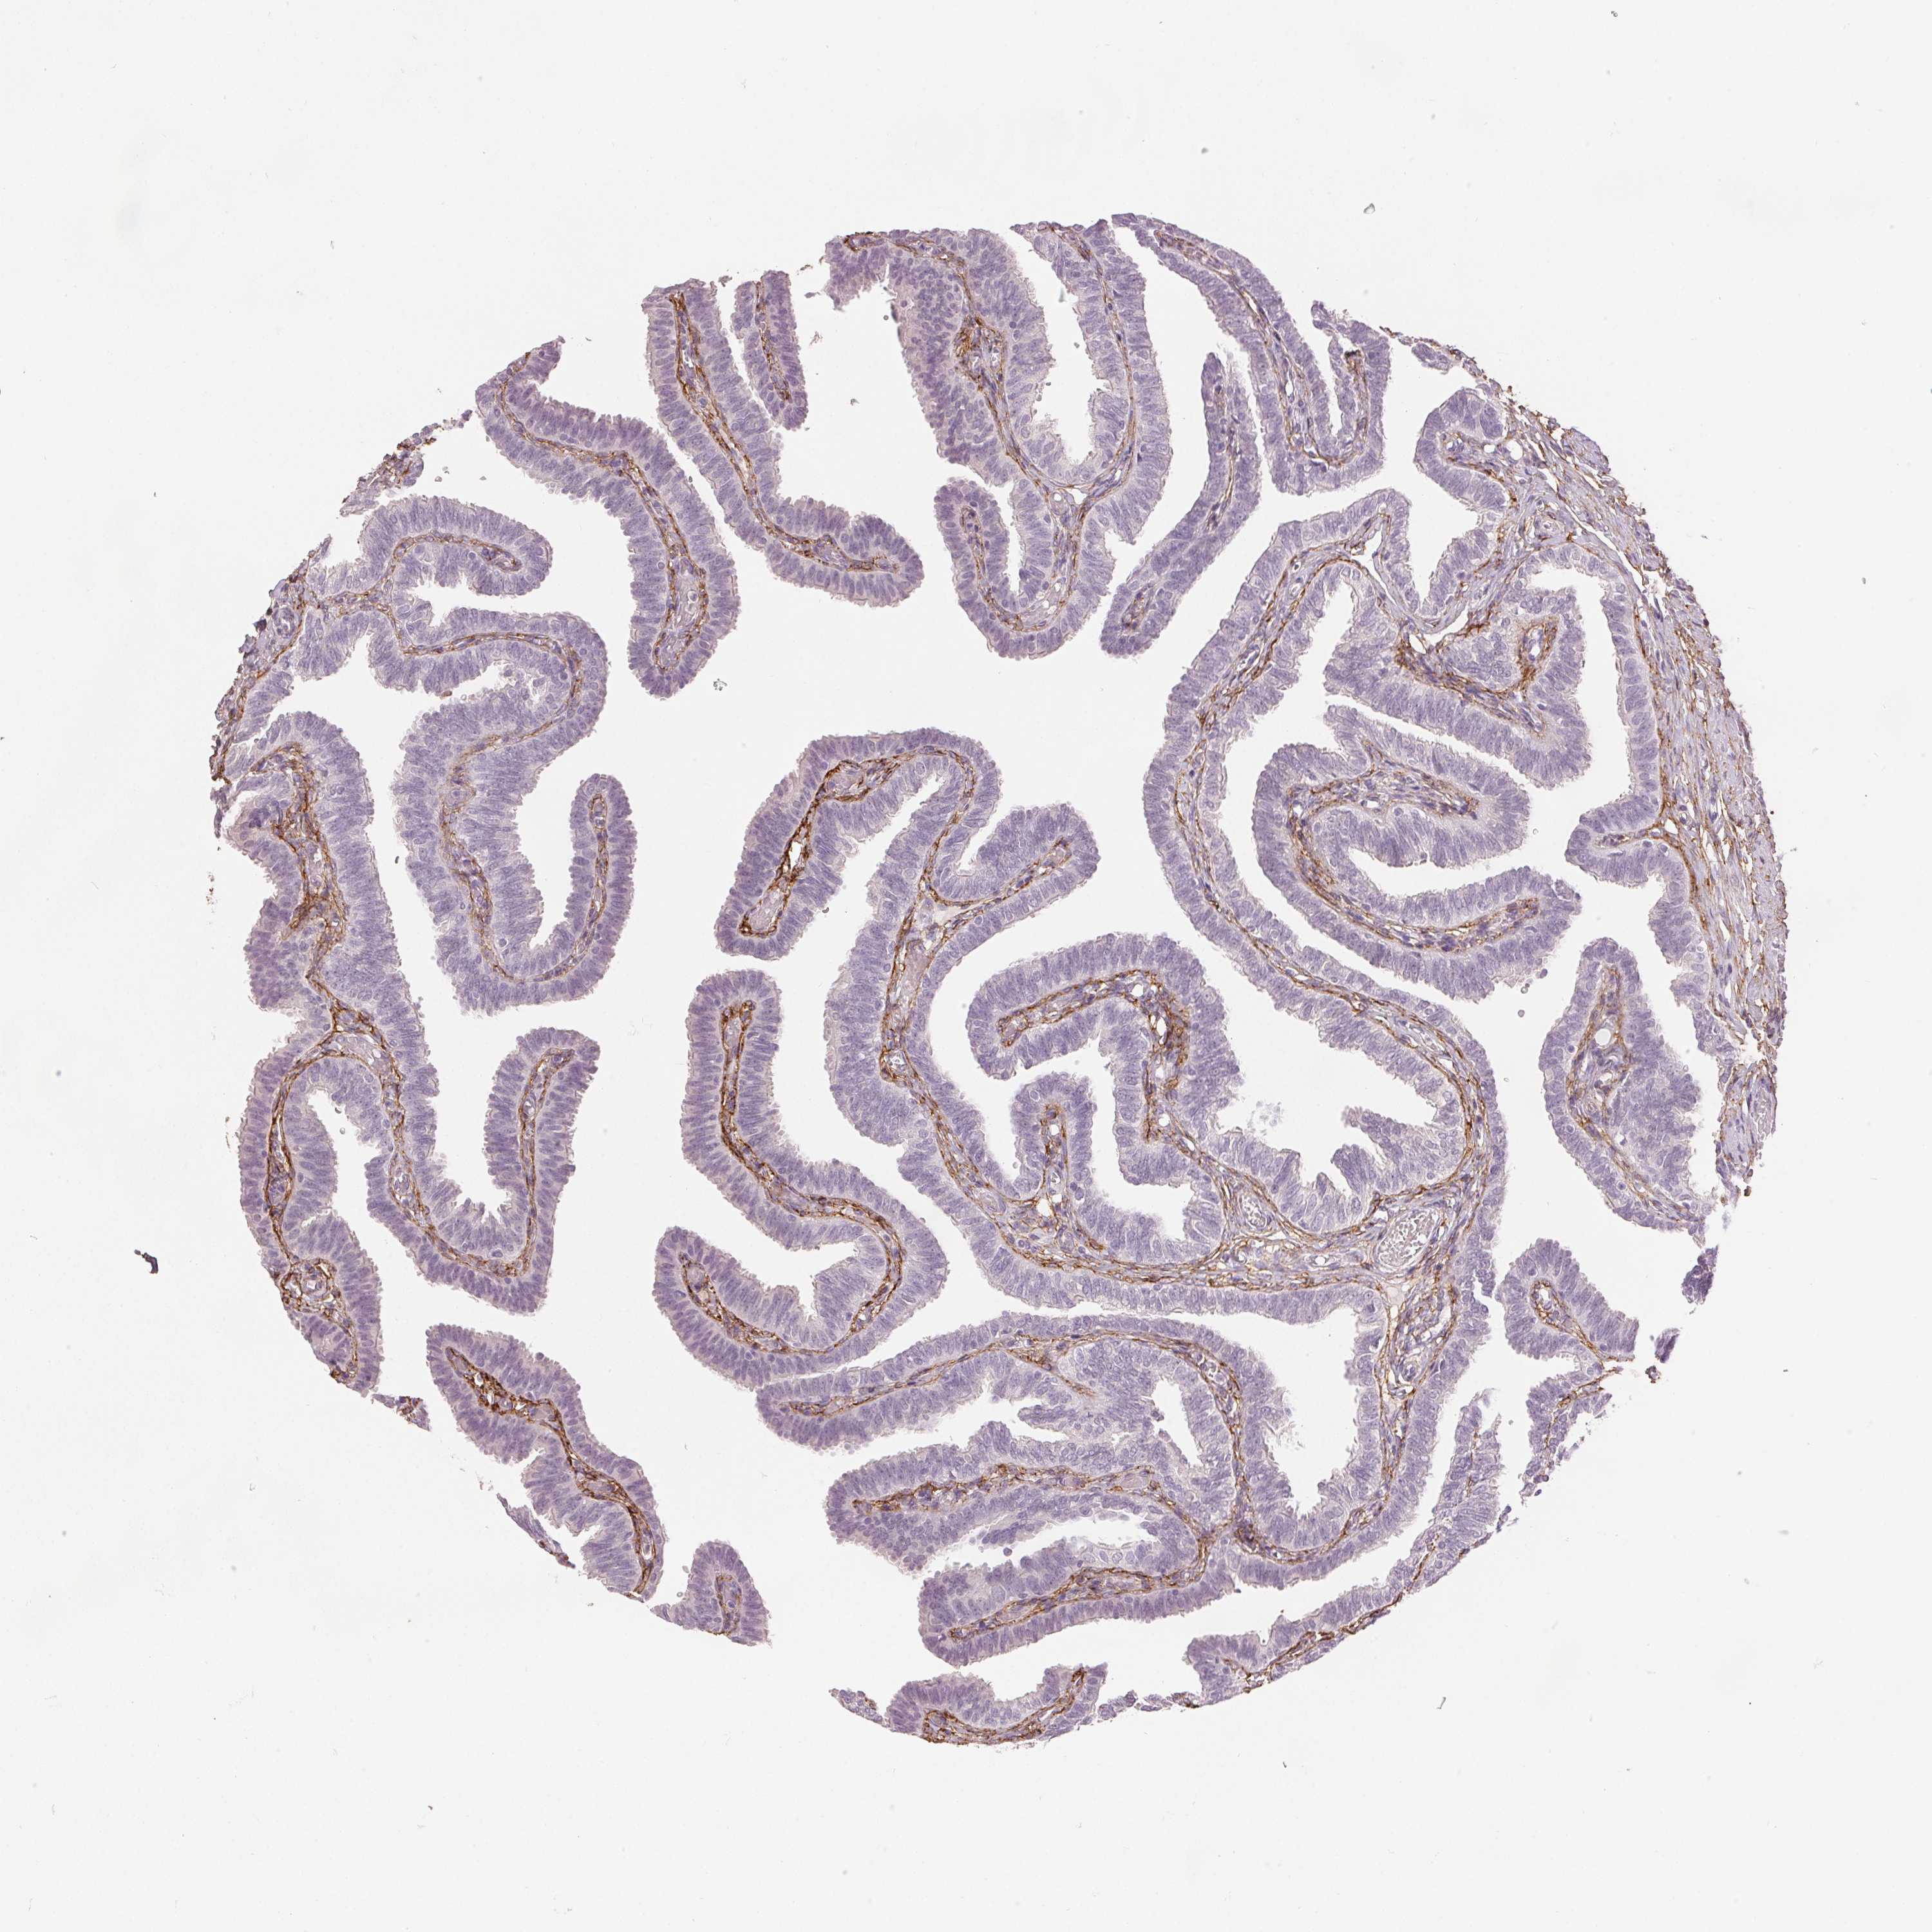

FALLOPIAN TUBE - Antibody stainingi

Antibody staining in the annotated cell types in the current human tissue is reported as not detected, low, medium, or high, based on conventional immunohistochemistry profiling in selected tissues. This score is based on the combination of the staining intensity and fraction of stained cells.

Each image is clickable and will lead to virtual microscopy that enables deeper exploration of all samples and also displays staining intensity scores, fraction scores and subcellular localization as well as patient and tissue information for each sample.

Antibody HPA017759Antibody HPA021057Antibody CAB002670Antibody CAB058696Antibody CAB068188Antibody CAB080202

Glandular cells LowNot detectedNot detectedNot detectedNot detectedNot detected